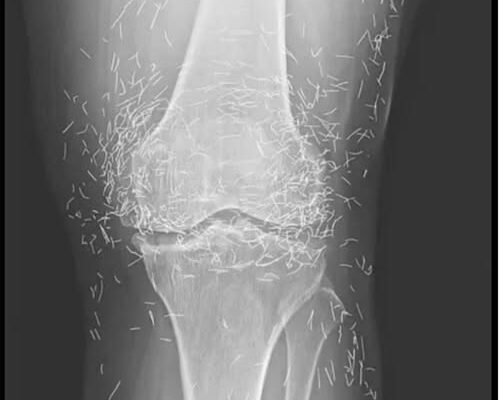

As doctors examined an X-ray image of the knees of an old woman experiencing severe joint pain, they found a gold mine: hundreds of tiny gold acupuncture needles left in her tissue.

In the woman’s acupuncture treatment, the needles, which were presumably made of gold, were intentionally left in her tissue for continued stimulation, the report says.

It could also make it hard for a doctor to read an X-ray. “The needles may obscure some of the anatomy,” Guermazi said.